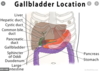

What are the 3 parts of the gallbladder?

1 - fundus

2 - body

3 - neck (also known as Hartmans pouch)

What are the antierior relations of the gallbladder close to?

- visceral surface of the liver

- anterior abdominal wall

- at the level of the the ninth right costal cartilage

What are the posterior relations of the fundus of the gallbladder close to?

= neck = the lesser omentum

= body = first and second parts of the duodenum

What are the inferior relations of the gallbladder close to?

- transverse colon